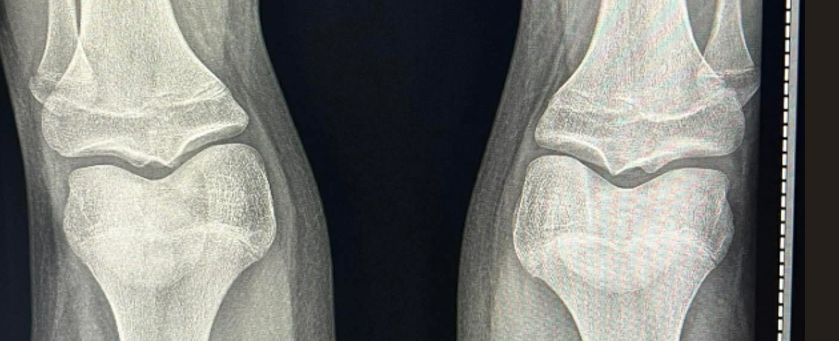

clearly open or am i wrong?i js got diagnosed ghd 2 months ago been on gh for 2 weeks View attachment 4968534View attachment 4968542View attachment 4968540 my retarded doctor said its too late shoudlve came last yearfor ai

brother are you blind its clearly almost completely fusedclearly open or am i wrong?

partialy closed or sumclearly open or am i wrong?

partialy closed or sum

What? Looking at your other pics your growth plates are almost fused, even with hgh your going to get to maximum 170-172cm, ai won't help much stop spamming the same thread or mods will ban your ass@Ahmed88 i just compleatly over? no ai

can i grow at least like 1.5 inches?What? Looking at your other pics your growth plates are almost fused, even with hgh your going to get to maximum 170-172cm, ai won't help much stop spamming the same thread or mods will ban your ass